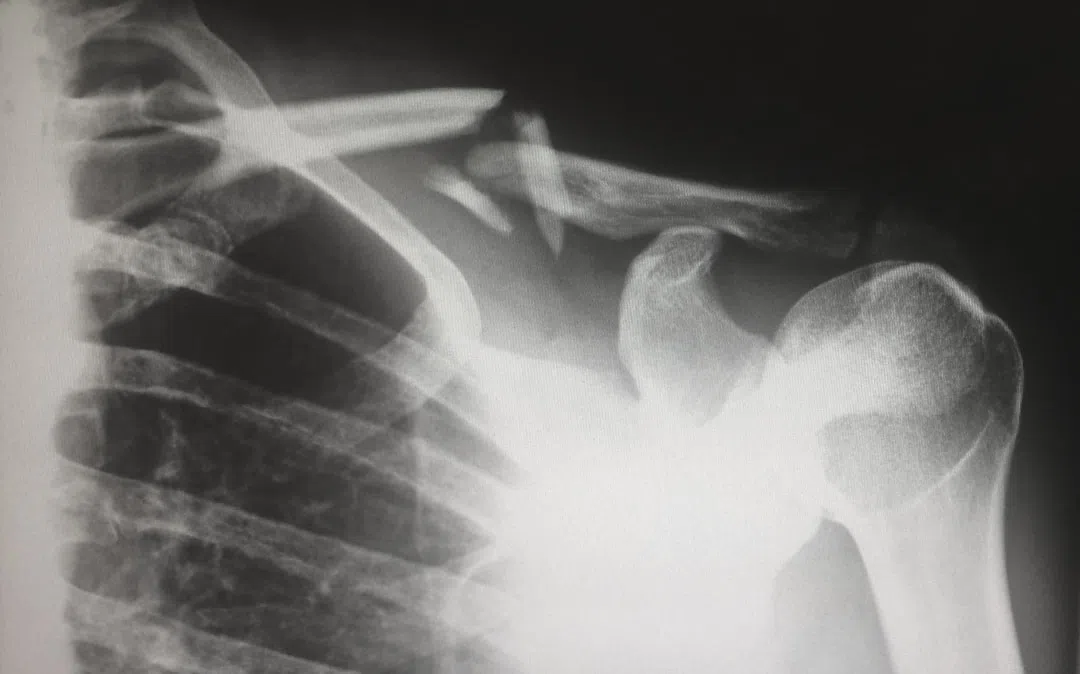

X-ray와 CT 검사

X-ray와 CT(컴퓨터 단층촬영)는 방사선을 사용하여 몸속의 구조를 확인하는 검사 방법입니다. 특히 뼈와 장기의 상태를 상세하게 볼 수 있어 골절, 폐 질환, 암 등 다양한 질환을 진단하는 데 유용합니다. 그러나 방사선에 노출되는 만큼 주의가 필요합니다.